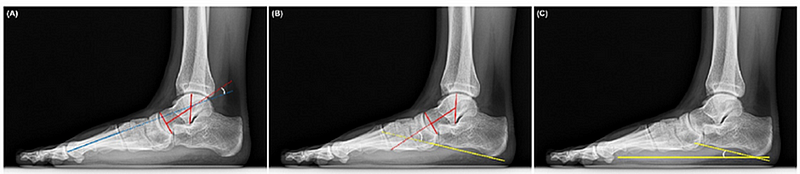

문진표에서 평발이 있다고 체크한 수검자가 저에게 오면, 먼저 족저경(거울)에 세워본 다음, 평발이 의심되면 X-ray를 촬영합니다. 그리고 X-ray에서 거골-제1중족골 각도종골경사각을 측정하여 현역 또는 4급 보충역 판정을 합니다. (그림 1) 대체로 많은 수검자들은 제가 내린 판정에 수긍하지만, 수긍하지 못하는 수검자가 있으면 X-ray를 보여주고 제가 각도를 측정하는 과정을 직접 보여주기도 했습니다. (그림 2)

그림 1. 족부 X-ray에서 확인되는 평발 각도 측정법: 정확한 병역판정의 기준점

(출처: Ryu, SM, et al. "Automated landmark identification for diagnosis of the deformity using a cascade convolutional neural network (FlatNet) on weight-bearing lateral radiographs of the foot." Computers in Biology and Medicine 148 (2022): 105914.)

(원문: https://pubmed.ncbi.nlm.nih.gov/35961089/)